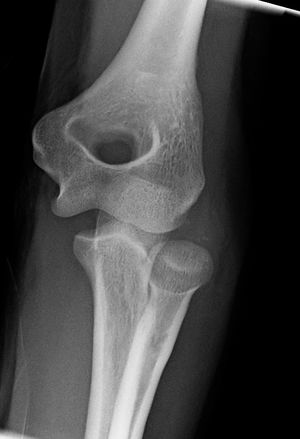

المرفق إنگليزية: Elbow هي عظمة مفصلية تربط عظمة العضد مع عظمتي الزند و الكعبرة. وتكون أماكن الالتقاء الثلاثة، ثلاثة مفاصل أصغر وتسمح هذه المفاصل الصغيرة بحركات معينة، حيث يسمح مفصلا العضد ـ الزند والعضد ـ الكعبرة للشخص بثني الساعد إلى أعلى وأسفل، بينما يسمح مفصلا الكعبرة ـ الزند والعضد ـ الكعبرة بدوران الساعد وكذلك راحة اليد أعلى وأسفل.

يحيط بمفصل الكوع كبسولة من نسيج متين. وتقوم هذه الكبسولة مع عدد من الأنسجة القوية الحبلية الشكل التي تُعرف بالأربطة بالمحافظة على العظام في أماكنها. ويعمل السائل الزيلي بمثابة مزلق لتقليل الاحتكاك عند الكوع.

| Joint | From | To | Description |

| humeroulnar joint | trochlear notch of the ulna | trochlea of humerus | Is a simple hinge-joint, and allows of movements of flexion and extension only. |

| humeroradial joint | head of the radius | capitulum of the humerus | Is a hinge-joint joint. |

| proximal radioulnar joint | head of the radius | radial notch of the ulna | In any position of flexion or extension, the radius, carrying the hand with it, can be rotated in it. This movement includes pronation and supination. |